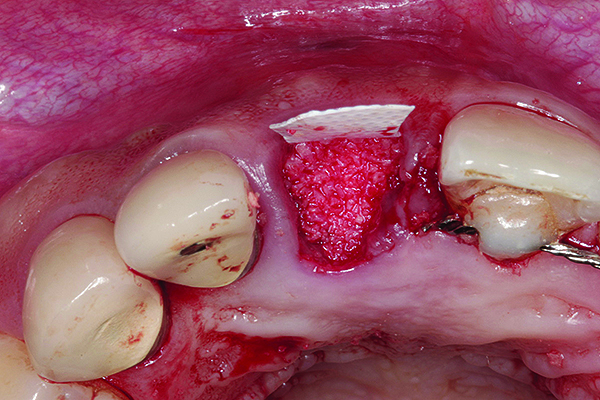

In cases with an incomplete facial plate, the ice cone technique was recommended.20 In this method, a collagen membrane was trimmed to the shape of an ice cone and placed into the socket against the inner aspect of the facial bone. The socket was filled with bone substitutes, and the coronal portion of the membrane was used to cover and protect the underlying bone substitutes. A non-resorbable PTFE membrane can be used for site preservation as well.21 This membrane, if secured to bone, can be left exposed, and epithelialization will occur over it. It was found that sockets grafted with a mineralized bone allograft and PTFE membrane had 47.4% new bone formation and 14.7% residual graft particles. In addition, there was minimum resorption of the buccal bone thickness, as indicated by a 0.3-mm horizontal bone resorption and a 0.25-mm vertical bone resorption.22 A recent systematic review reported that the use of PTFE membranes in ridge preservation shows potential in maintaining ridge dimensions23 and possibly aiding in increasing the zone of keratinized mucosa. Therefore, the use of PTFE membrane may be preferred in ridge preservation of sites in the esthetic zone. Figure 1 and Figure 2 illustrate the use of PTFE membrane in ridge preservation for implant replacement in the esthetic zone. Other authors have also attempted primary closure of the socket or to improve the ridge topography with soft-tissue grafts, but it has not been proven to be effective in increasing bone regeneration.18

Placement of PTFE membrane to form the missing buccal bone. - See more at: http://cdeworld.com/courses/4756-Site_Preparation_for_Implant_Replacement_in_the_Esthetic_Zone#sthash.O5zxOUde.dpuf

Figure 1

In sites with an intact and thick (≥2 mm) buccal bone, no grafting is required. A collagen plug may be used for hemostasis at the site of extraction. In sites with an intact and thin (<2 mm) buccal bone, the mineralized bone allograft-plug augmentation technique is preferred because of its effectiveness. For sites with no or incomplete buccal bone, the PTFE membrane can be placed between the bone and buccal soft tissue to form the buccal border. It is subsequently folded over the entrance of the socket, thus serving to contain and protect the bone graft that is placed into the socket. The PTFE membrane is removed 4 weeks after placement,23 and soft tissue will granulate over the site, thus increasing the soft-tissue thickness, which is beneficial for an esthetic implant restoration. Simultaneous or staged GBR, onlay grafts, ridge expansion, or distraction osteogenesis may be used to further augment the residual ridge if necessary. Soft-tissue augmentation can be performed before ridge augmentation or at implant uncovering stage, depending on the soft tissue thickness and width of keratinized mucosa.